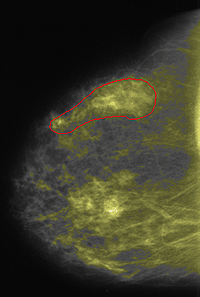

Holding the mouse button down, outline an area that contains densities you wish to identify (eg. for mammogram sessions, exclude the pectoralis muscle, any scarring artifacts, and non-dense areas that are colored when you apply the tint, but that you do not consider to represent densities). In order to close a region you must return to the point at which you started outlining. You can accomplish this by returning to within a few pixels of the starting point, or by double clicking the mouse, or by pressing the space bar on the keyboard. Check that there is some quantity of pixels appearing in the status line at the top of the window after "ROI#n:" where n represents the ROI you are creating.

Regions are drawn as a floating layer above the image. The perimeter pixels of the region are displayed in outline if you zoom in far enough. These perimeter pixels are INCLUDED in the region. A region can consist of a single pixel if necessary.